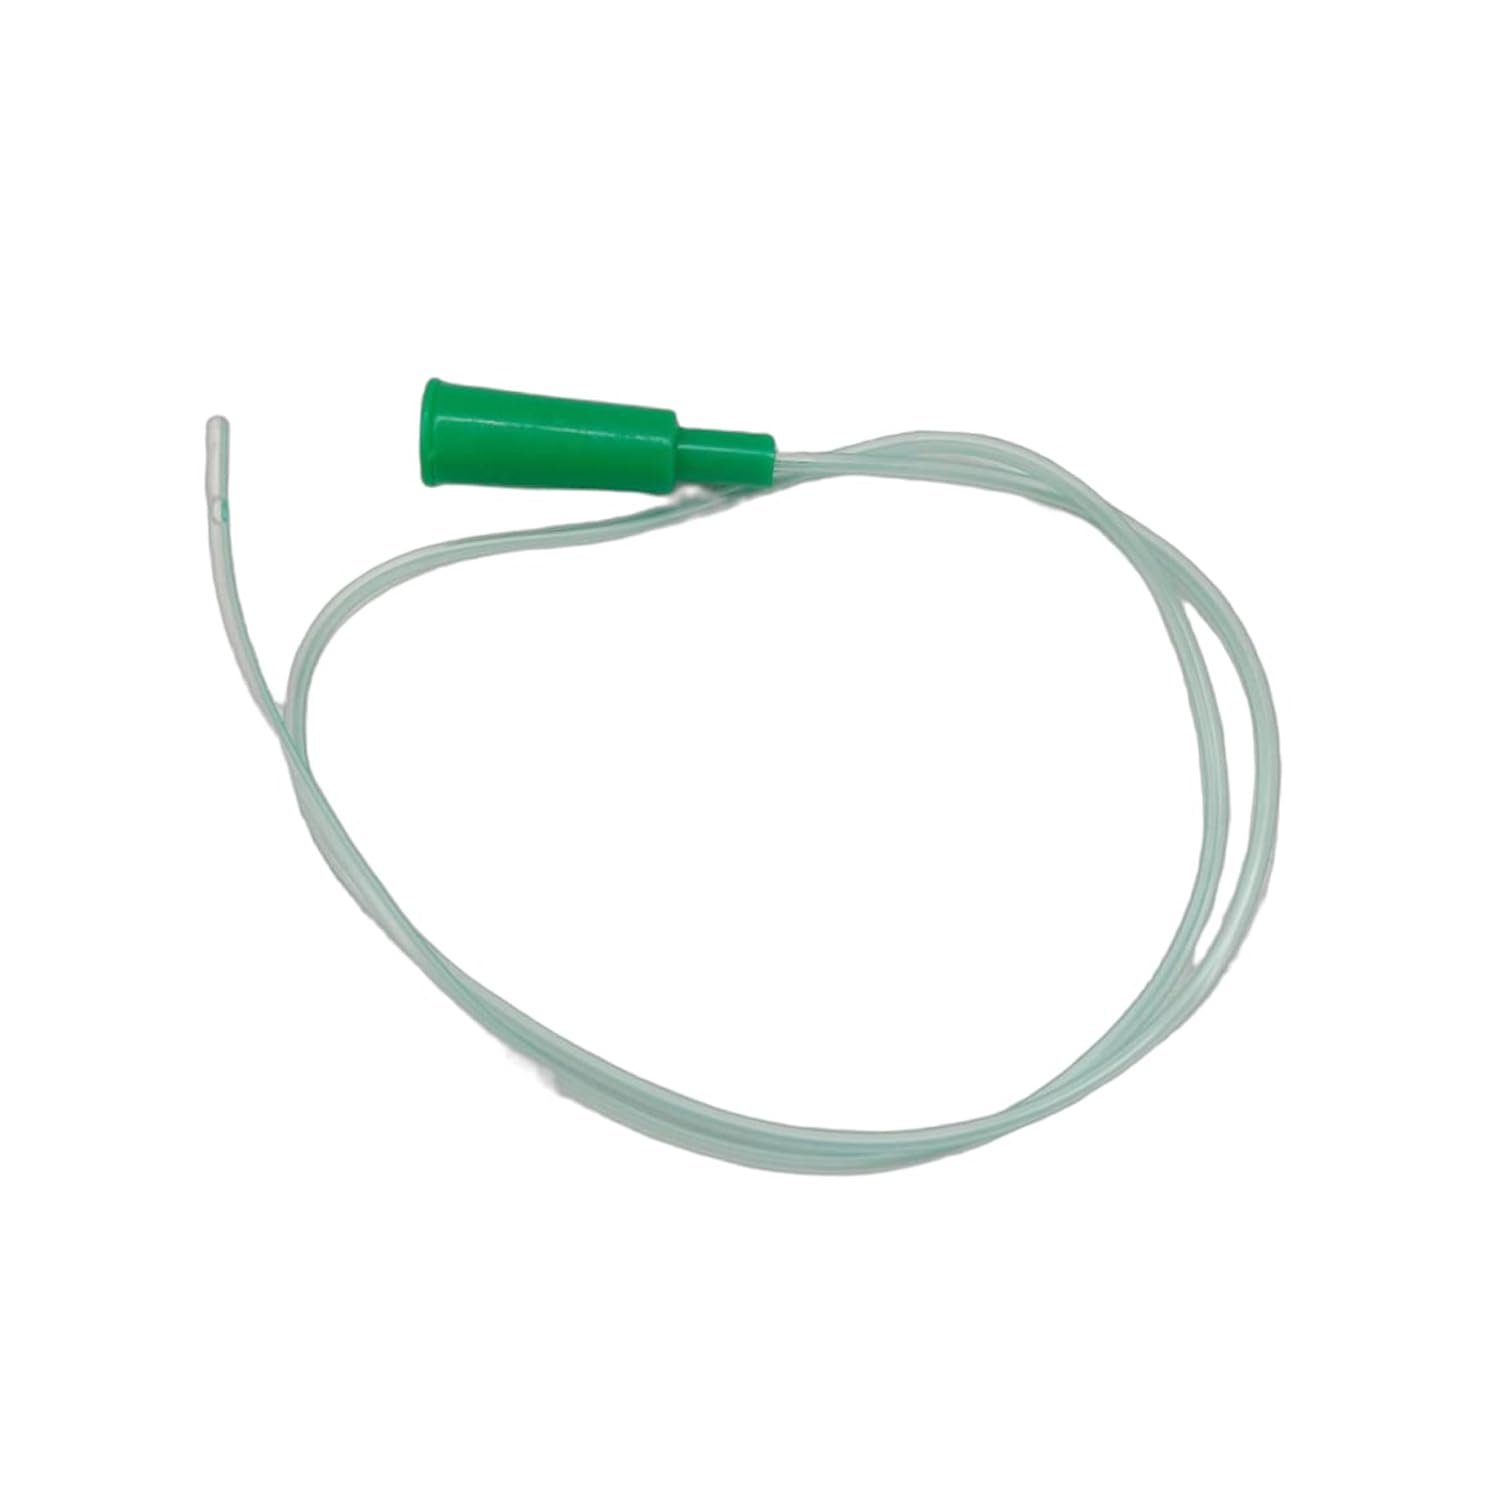

Suction Catheter

Suction CatheterOur ProductsFrom SurgicaveUplode:9 months ago from India